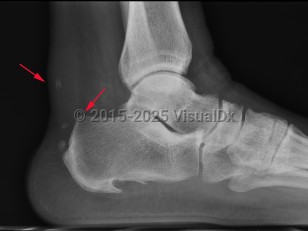

Haglund deformity is enlargement of the posterosuperior tuberosity of calcaneus. Retrocalcaneal bursitis is inflammation of the space between the anterior aspect of Achilles tendon and posterior aspect of calcaneus.